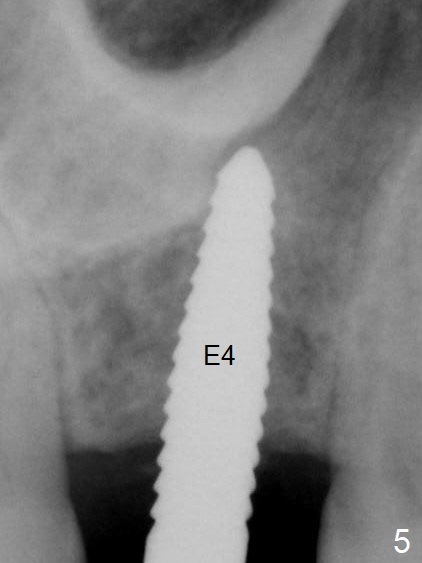

A 54-year-old man has lost the tooth #3 for 6 months with complicated sinus floor morphology (Fig.1 red dashed line (one of 2 outlines), bone height ~ 7 mm). Initial osteotomy depth is ~ 6 mm (Fig.2,3 with 1.2 mm initial drill and DIO Bone Expander 1 (E1 with diameter 1.0/1.6 mm). Following change in the trajectory, E2 (1.3/2.3 mm) is used for ~ 8 mm (Fig.4). After application of E4 (2.4/3.7 mm, Fig.5) and E5 (3.0/4.4 mm) for ~ 12 mm, the sinus membrane is found to have perforated. With placement of collagen membrane and cortical allograft (Fig.6 *), a 5x8.5 mm Hiossen implant is placed with >50 Ncm.